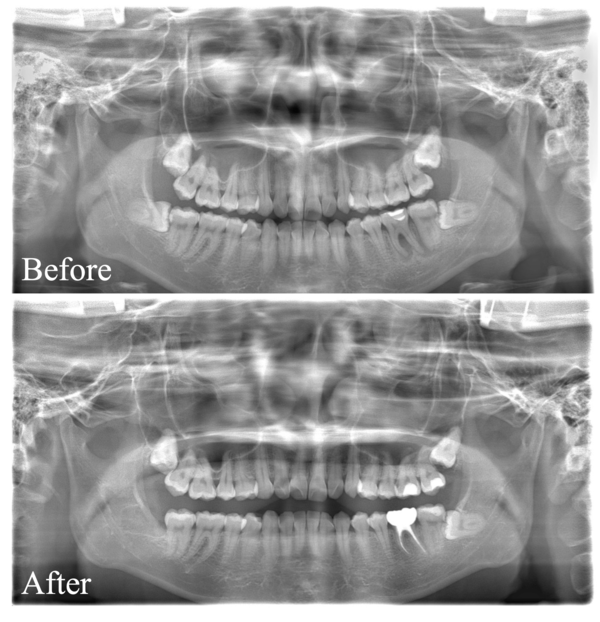

こちらが初診時のX線写真です。

X線で左下6番周囲の骨が明らかに欠損していることがわかります。この段階で神経が壊死している(歯髄失活)可能性、歯周病の可能性などが考えられ、様々な検査を行いました。

こちらは比較用初診時X線写真です。

治療前後を比較してみると、順調に骨が回復してきていることがわかります。しかし、まだ根と根の間、根分岐部と呼ばれる部分の骨が完全には上がってきておりません。

このまま骨が上がらない可能性もありますが、今回は上がってくる可能性が高いと判断し、患者様とも確認をしつつ引き続き年単位で経過を見ていきます。